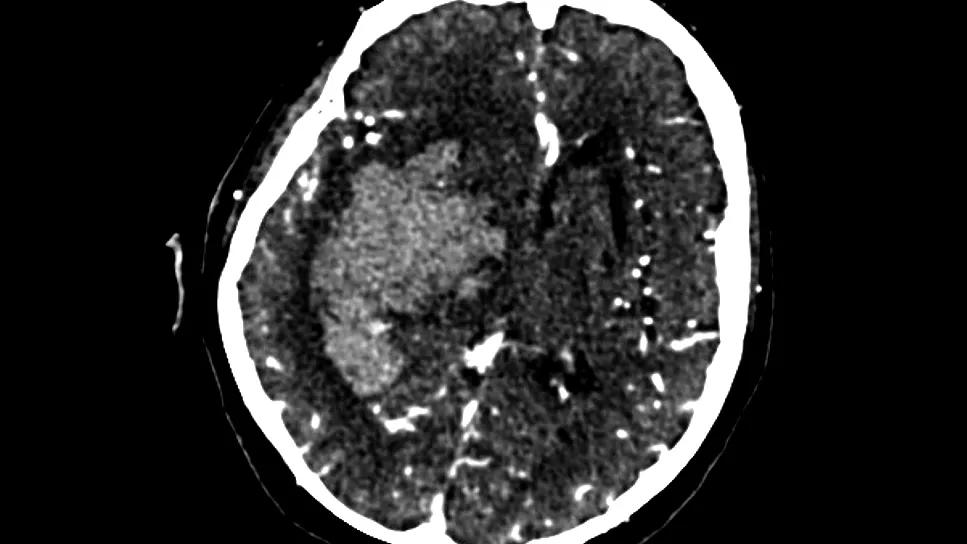

intracranial hemorrhage in the basal ganglia as shown on a brain scan

A computational morphological model of basal ganglia intracranial hemorrhage (ICH) based on preoperative CT angiography can serve as a prognostic tool to help determine candidacy for minimally invasive surgical evacuation. So suggests a new study that describes the model design and its potential utility compared with traditional prognostic tools used for patients with a basal ganglia ICH. The single-center Cleveland Clinic study was published in the Journal of Neurointerventional Surgery.